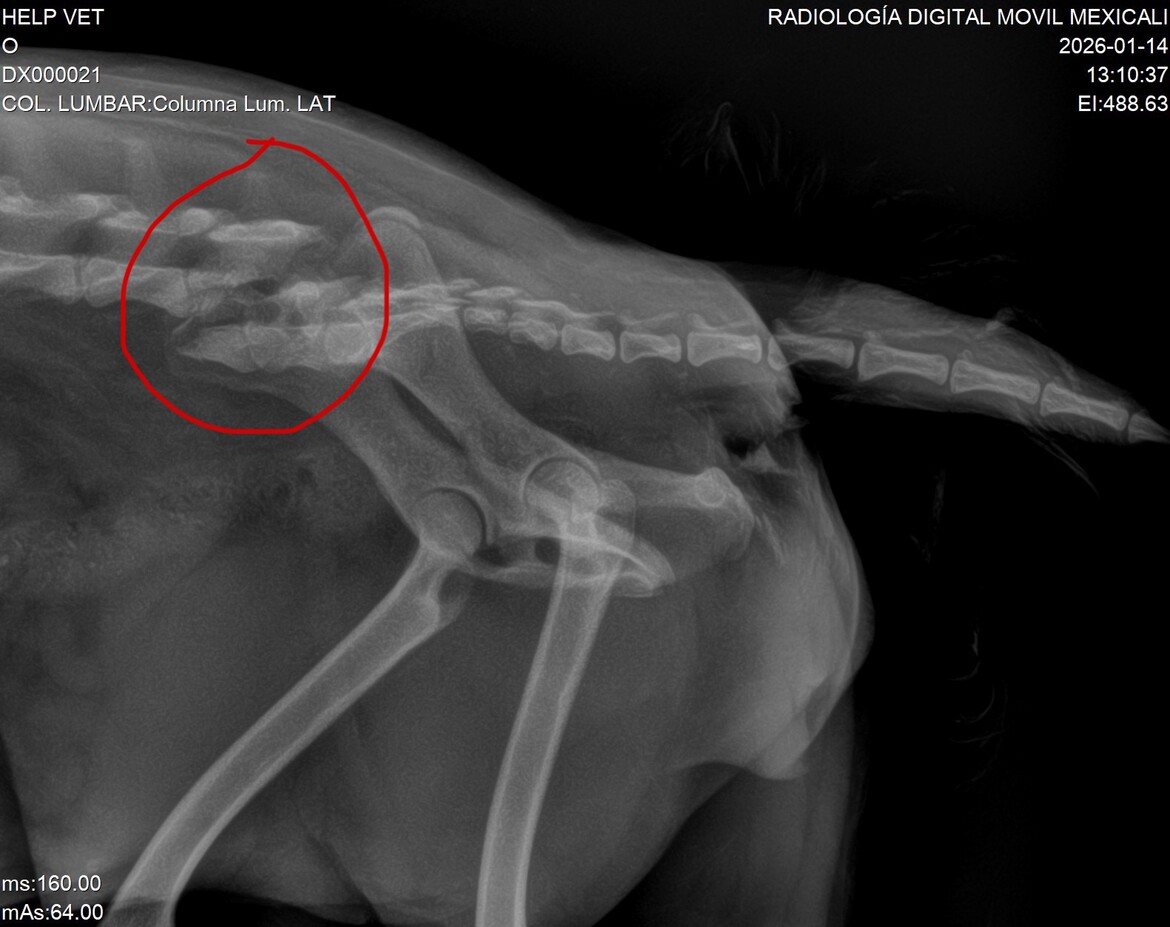

She was taken to HelpVet Veterinary Clinic in Mexicali, where the doctors immediately evaluated her, ruled out internal bleeding, and began treatment for pain and inflammation. X-rays confirmed a spinal fracture. Since then, she has been receiving medical care, and medications have been continuously prescribed and paid for as part of her stabilization.

The veterinarians believe Magüi has a real chance to recover and walk again, but she will need a specialized spinal surgery using bone cement, followed by ongoing medication and post-operative care. These costs go beyond what one person can cover alone.